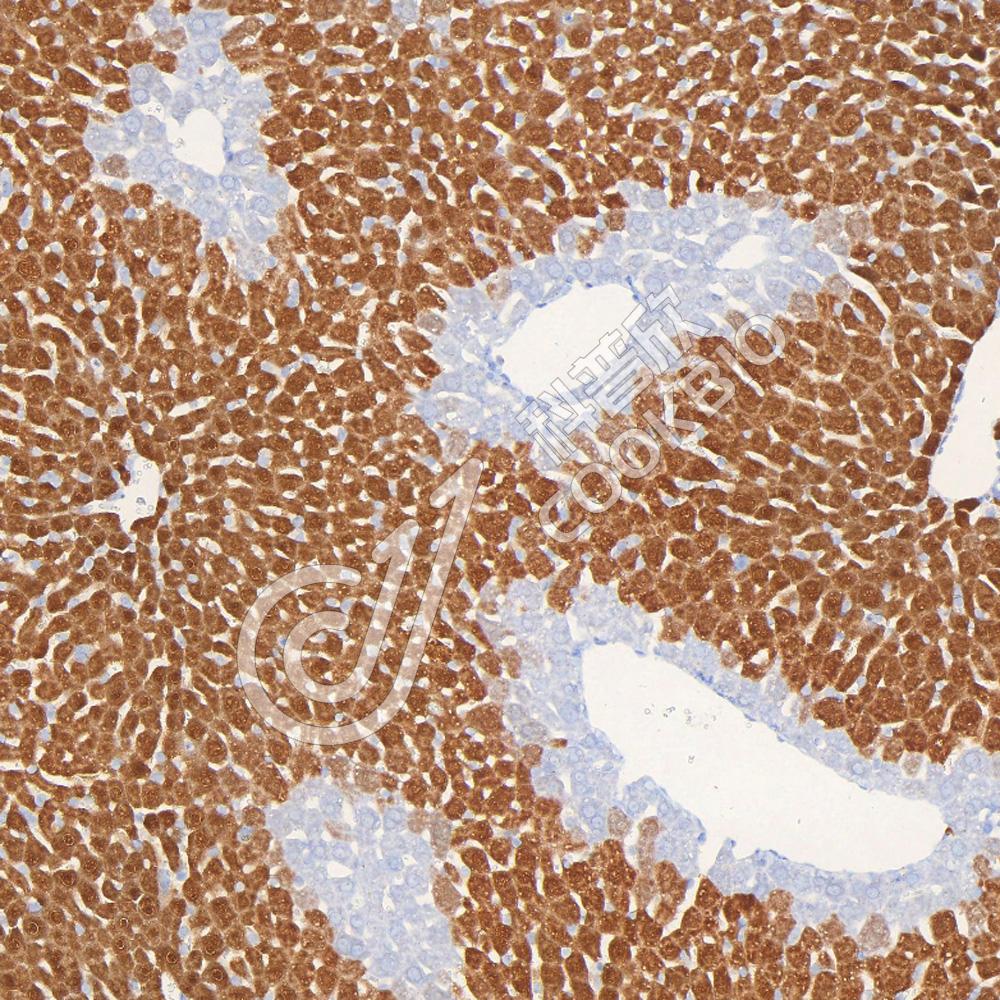

IHC检测Arginase 1蛋白(货号 K545855).

样品: 人肝癌, 4%多聚甲醛 (货号KSG1101) 固定12-24小时.

抗原修复: 柠檬酸抗原修复液(干粉, pH 6.0) (KSG1201), 高压锅均匀喷气计时2分钟.

—抗: 1: 1500稀释, 4℃ 孵育过夜.

二抗: S-vision免疫组化多聚二抗(山羊抗兔),即用型 (货号KB3906), 室温孵育20分钟.